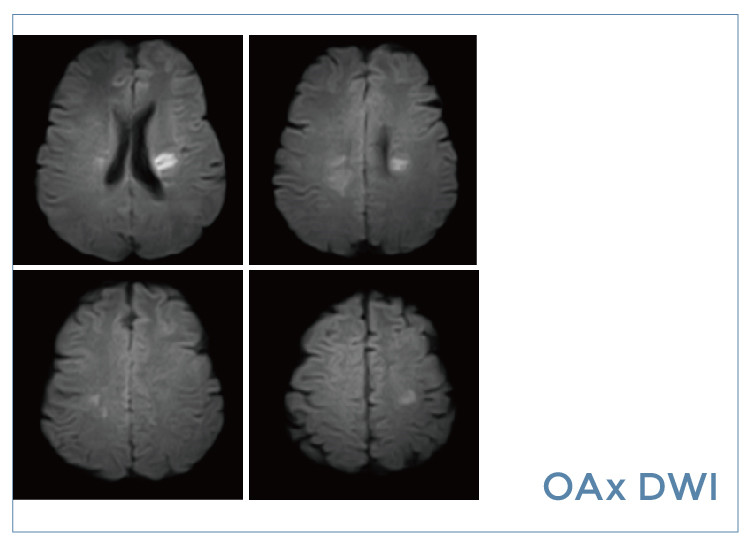

【朗润影像档案】磁共振影像病例分享(编号20190823)